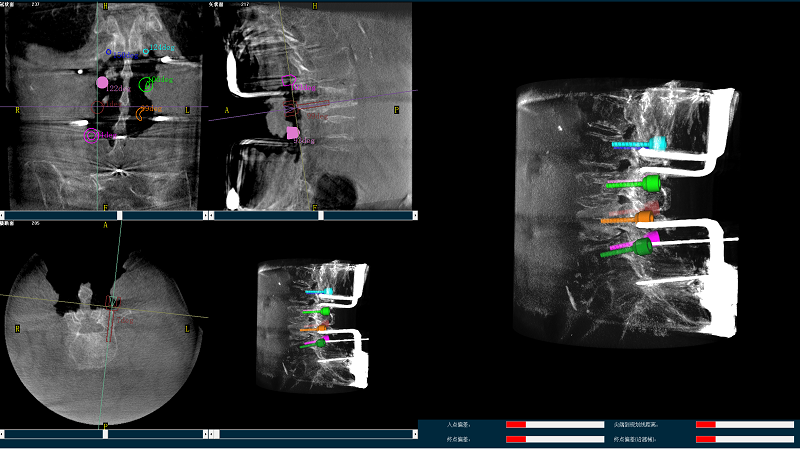

三維圖像

(2)使用普愛醫(yī)療平板三維C形臂掃描患者,得到術(shù)中三維圖像并傳送至骨科機器人導(dǎo)航系統(tǒng)。骨科機器人導(dǎo)航系統(tǒng)基于高清術(shù)中三維圖像進行手術(shù)規(guī)劃。

手術(shù)規(guī)劃圖像

(4)在骨科機器人導(dǎo)航系統(tǒng)輔助下,一次性準(zhǔn)確植入8枚椎弓根螺釘。